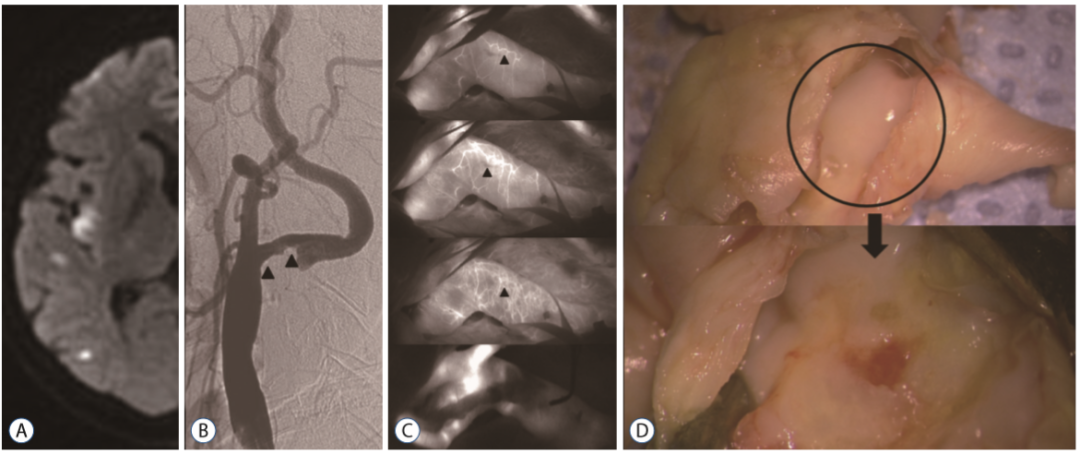

吲哚菁绿视频血管造影(Indocyaninegreen video angiography,ICG-VA)通常用于颅内动脉瘤手术、搭桥手术和颈动脉内膜切除术(CEA)中,以确定血管通畅程度并实时观察损伤状态。在本实验中,ICG-VA主要用于确定滋养血管类型。

内源血管滋养管(Vasa vasorum internae,VVI),直接源自于血管腔,进入血管壁中。

自2015年9月至2017年12月,纳入69例行CEA的患者(症状性患者,狭窄程度≥50%;无症状患者,狭窄程度≥70%)。CEA期间,在切开颈动脉之前,由一名麻醉师在进行血管造影时静脉注射ICG,分析造影结果,确定管腔狭窄情况以及滋养血管类型。

所有患者均观察到了滋养血管,其中外源血管滋养管(VVE)11例(16%),内源血管滋养管(VVI)57例。VVE型与颈动脉易损斑块(90.9%,p = 0.017)密切相关。与稳定斑块相比,不稳定斑块中观察到CD68染色的巨噬细胞和CD117染色的肥大细胞的频率更高。